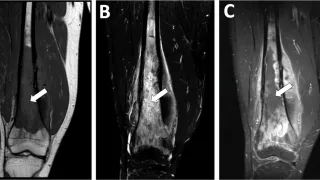

手術日+728日目 2026/2/25(水)(筋肉内神経鞘腫)